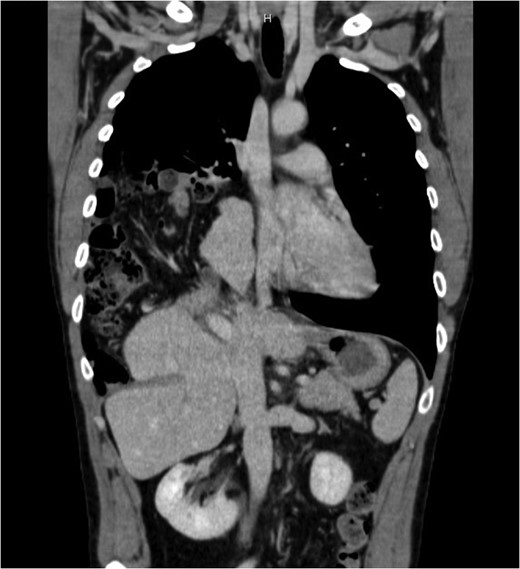

Thorax and abdominal CT showing the dislocation of right upper abdominal viscera

He was then admitted to the surgery department for a laparoscopic exploration that confirmed the radiological finding of inveterate right diaphragmatic hernia with an 8 cm defect. Because of the impossibility to reduce the liver in abdomen, due to the thoracic adhesions, a right anterolateral thoracotomy was then performed. The liver was uneventfully reinstated and colon and small bowel were replaced in anatomical position. The defect was repaired by dual mesh patch (15 × 25 cm). The postoperative course was uneventfully. Postoperative oxygen saturation was normal and a chest X-ray was performed before discharge and revealed complete re-expansion of the lung. The patient was discharged on the ninth postoperative day. The follow-up is negative for signs of recurrence after 2 years.